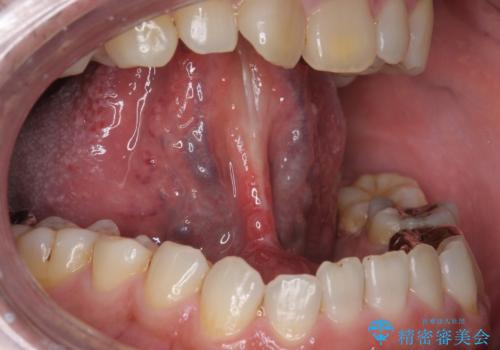

術前に舌の動きを確認した後、局所麻酔下での施術となりました。

局所麻酔下にて施術しました。

術後1週間で抜糸、約2週間で完全に治癒していきました。